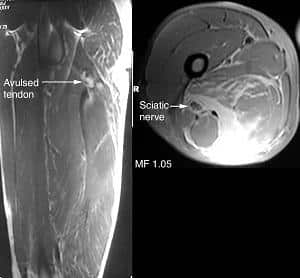

- МРТ предоставляет трехмерное изображение, позволяющее увидеть скопление жидкости, локализацию, давность и степень повреждений.

На основе этих исследований врач подтверждает наличие синдрома хамстринга и определяет его степень.

В случаях тяжелого повреждения лечение требует хирургического вмешательства. Показаниями для операции являются полное или частичное отрывание связок и мышц от седалищной кости, а также хронический синдром с образованием рубцов.

Во время операции хирург устраняет болевой синдром, удаляет рубцы и сдавливание седалищного нерва, фиксирует правильное анатомическое положение суставно-связочного аппарата и восстанавливает мышечные ткани.